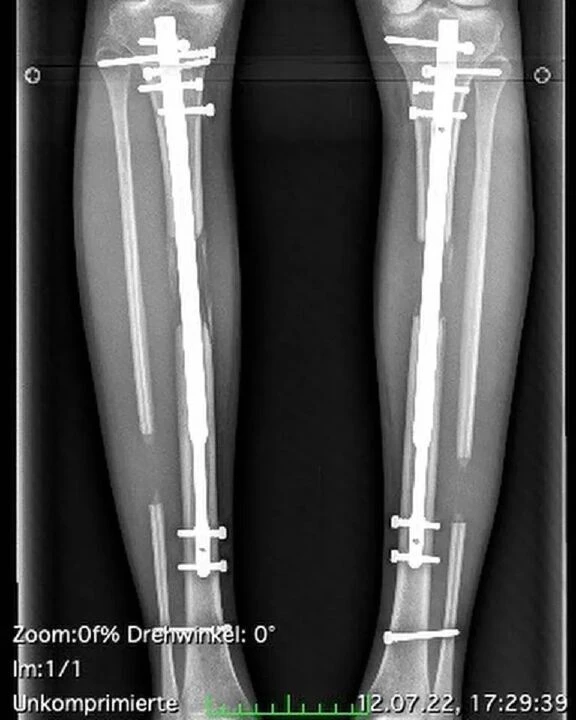

Fischer'ın son ameliyatında uyluk ve alt bacak kemiklerinin kesildi ve kaval kemiğine ayarlanabilir teleskopik çubuklar takıldı. Sağlık görevlileri, bacakları daha uzun olana kadar bu çubukları çevirdi. Haziran ayında, yeni kemik dokusunun büyümesini sağlayan teleskopik çelik çubukları çıkarmak için yapılan son sekizinci ameliyatın ardından Freiburg'daki Üniversite Hastanesi'nden ayrıldı. Bacaklarındaki kemikler her birkaç santim büyüdüğünde, cerrahlar daha fazla büyümeyi teşvik etmek için aralığı genişletiyorlardı.